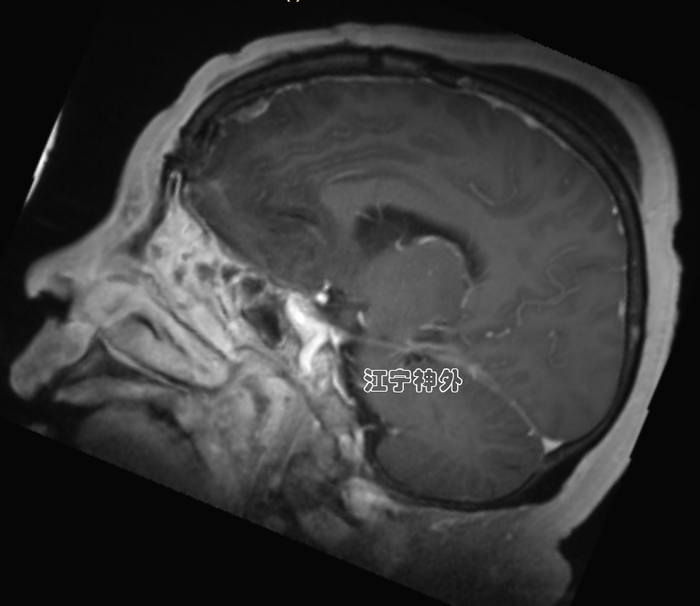

郑学胜团队予以术前磁共振检查发现,前颅窝底巨大脑肿瘤,伴有大片脑水肿,双侧侧脑室和第三脑室明显受压变小,下丘脑、左侧基底节等神经结构亦受明显推挤。肿瘤血供丰富,与双侧大脑前动脉关系复杂。